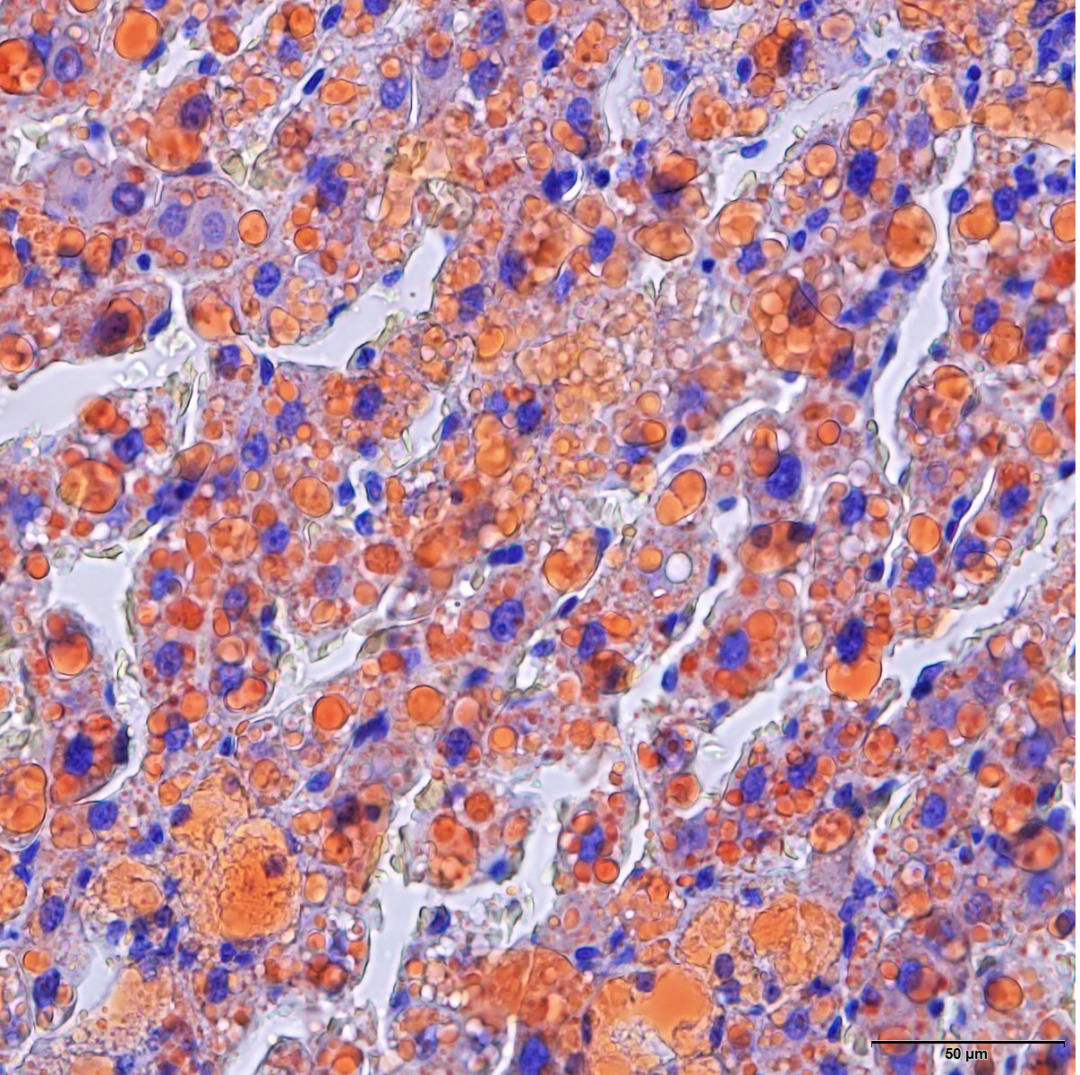

5-羟色胺(5-HT)能神经元位于脑干中缝核和网状结构的相邻细胞翼,广泛投射至中枢神经系统的每一主要亚结构,其中释放的5-HT靶向14种不同的受体类型。在背侧中缝核(DRN)中5-HT神经元占所有神经元的三分之二,且提供了前脑约70%的5-HT。5-HT能神经元不仅可以释放5-HT(又称血清素)作为神经递质,同时也释放谷氨酸。三种谷氨酸囊泡转运体VGluTl,VGluT2以及VGluT3负责转运谷氨酸到突触囊泡里,其中的VGluT3在5-HT能神经元中呈高表达。 所有5-HT神经元最显著的特征是生物合成5-HT。5-HT在化学上属吲哚胺类化合物,由吲哚和yi胺两部分构成。生物合成是以色氨酸为前体,经过色氨酸羟化酶(TPH)和5-羟色胺酸脱羧酶的作用生成的。色氨酸羟化酶2(TPH2)和芳香族氨基酸脱羧酶(AADC)是直接催化大脑5-HT合成的两种末端效应物。5-HT神经传递需要再摄取和囊泡转运活动。高亲和力5-HT转运蛋白(SERT,SLC6A4)用于5-HT再摄取,囊泡单胺转运蛋白2(VMAT2,Slc18a2)用于装载囊泡。5-HT合成、再摄取和囊泡转运的共同末端效应物一起构成了一组5-HT途径蛋白,其激活赋予5-HT型递质同一性。PET1除了在5-HT神经元出生时控制5-HT途径基因的诱导外,它还可能直接控制支持5-HT神经元成熟的基因表达轨迹。